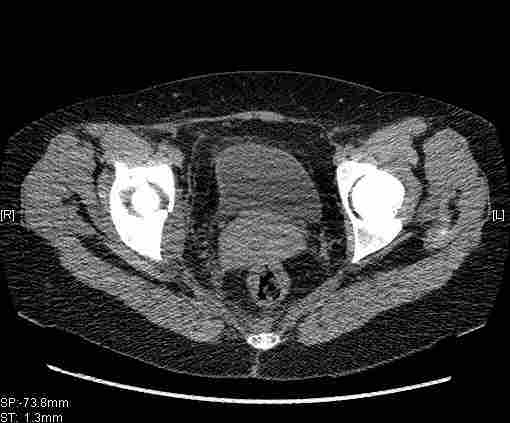

Удалось сегодня вывести пациентку в соседнюю больницу, где есть кт. Срезы сделаны только горизонтальные.